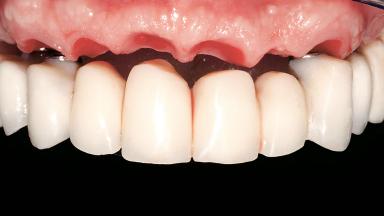

Immediate Loading of Six Implants in the Maxilla and Final Restoration with a Full-Arch CAD/CAM Zirconia FDP

A 63-year-old male patient was referred for a consultation and treatment of partial edentulism in the maxilla. The patient presented with residual anterior teeth and declined a partial removable prosthesis. He reported that the maxillary posterior teeth had been extracted due to mobility and periodontal disease two months before the consultation. The patient’s chief complaint was that his residual maxillary teeth were mobile and that he was unable to chew. The patient’s desire was a stable and comfortable fixed maxillary rehabilitation. The patient was a light smoker (fewer than 10 cigarettes/ day), and his medical history was without significant findings. He was not on any regular medication at the time of consultation. The extraoral examination revealed a normal physiognomy with a correct distribution of the facial thirds. The patient presented a low lip line, and the transition line between teeth and soft tissues was not exposed during a forced smile.

Abutment Type CAD/CAM

Prosthesis Type FDP

Lip Line No exposure of papillae Exposure of papillae Full exposure of mucosa margin